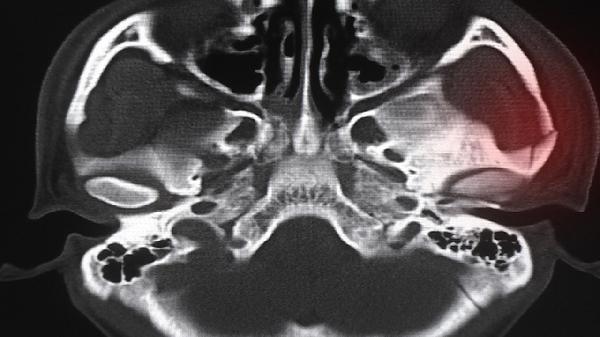

5、促进骨折愈合

接骨木所含的硅元素能促进成骨细胞活性,加速骨痂形成。临床常用于骨折中后期康复治疗,多与骨碎补、续断等续筋接骨药材配伍使用,但骨折初期须先进行正规骨科处理。